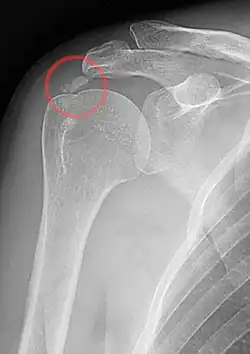

Tendinitis calcarea

Tendinitis calcarea is een peesontsteking in de schouder. Deze ontsteking wordt veroorzaakt door calciumfosfaat in of rondom de betreffende pees, meestal de pees van de musculus supraspinatus zodanig dat de schouder pijn gaat doen bij bepaalde bewegingen. Vaak ontstaat er ook een bewegingsbeperking in de schouder, mede door de pijn.